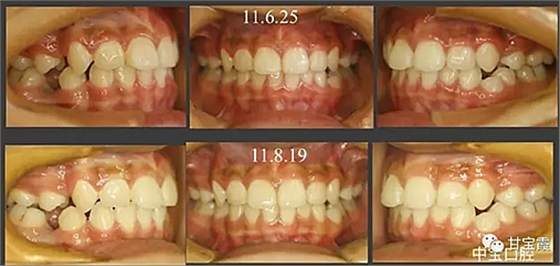

經(jīng)過三年零九個月的看護,最終戴上了固定矯治器,但是大家不難發(fā)現(xiàn),孩子的牙齒已經(jīng)排齊,上下中線也基本對齊,面型也好看多了,這樣矯正就變得簡單,療程自然縮短,孩子也不遭罪了。

這個故事告訴我們,只有家長早點把孩子帶給正畸醫(yī)生檢查,才能早期發(fā)現(xiàn)早期治療。起到了事半功倍的效果。矯正以后還不容易復發(fā),因為從08年的初診到11年戴矯正器這三年多的時間里,孩子的牙齒是自己長好的。